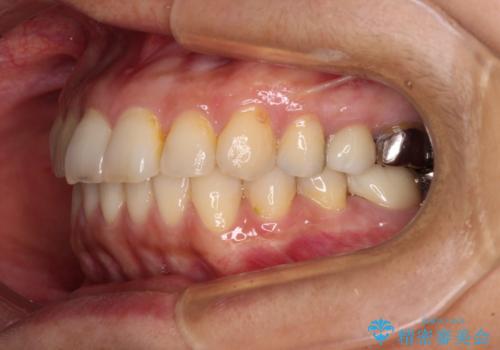

後戻りは軽微であったため、インビザライン・ライトにて歯列を整えました。

矯正治療後には、左下奥歯の症状がないことを確認し、セラミッククラウンにて補綴治療を行うこととしました。

矯正治療後のレントゲン写真では、根尖部に認められた病変(骨の溶けていた像)は消失していることが分かりました。